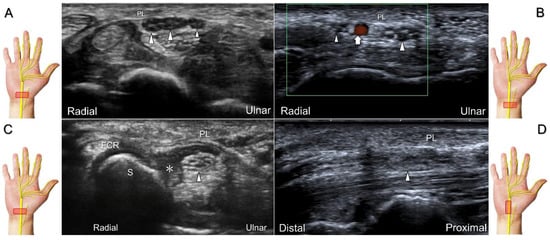

Figure 2. Sonographic/normal imaging of the median nerve from the inlet (A) to the outlet (B) of the carpal tunnel. Hypertrophy of the flexor retinaculum at both the inlet (C) and outlet (D) of the carpal tunnel. Asterisk: median nerve; small white arrowheads: normal flexor retinaculum; large arrowheads: hypertrophy of the flexor retinaculum. FCR: flexor carpi radialis; S: scaphoid; P: pisiform; T: trapezium; H: hook of the hamate.

The transducer can be placed in the axial plane on the distal one-third of the forearm with the forearm supinated. The median nerve travels between the flexor digitorum superficialis and flexor digitorum profundus muscles. It gradually runs superficially to enter the carpal tunnel. The carpal tunnel inlet is defined as the plane crossing the scaphoid and pisiform (Figure 2A), whereas the plane linking the trapezium and hook of the hamate serves as the carpal tunnel outlet (Figure 2B).

Clinical Implication

Carpal tunnel syndrome is the most common entrapment neuropathy whereby the median nerve is entrapped by various causes, like hypertrophy of the flexor retinaculum (Figure 2C,D) and compression from the accessory muscles, swollen tendons, ganglions, and bony fractures within the tunnel. Ultrasonographic changes encompass swelling proximal to the entrapment site (Figure 3A), flattening over the entrapment site (Figure 3B), intraneural hypervascularity (Figure 3C), and focal loss of the trimline pattern (Figure 3D).